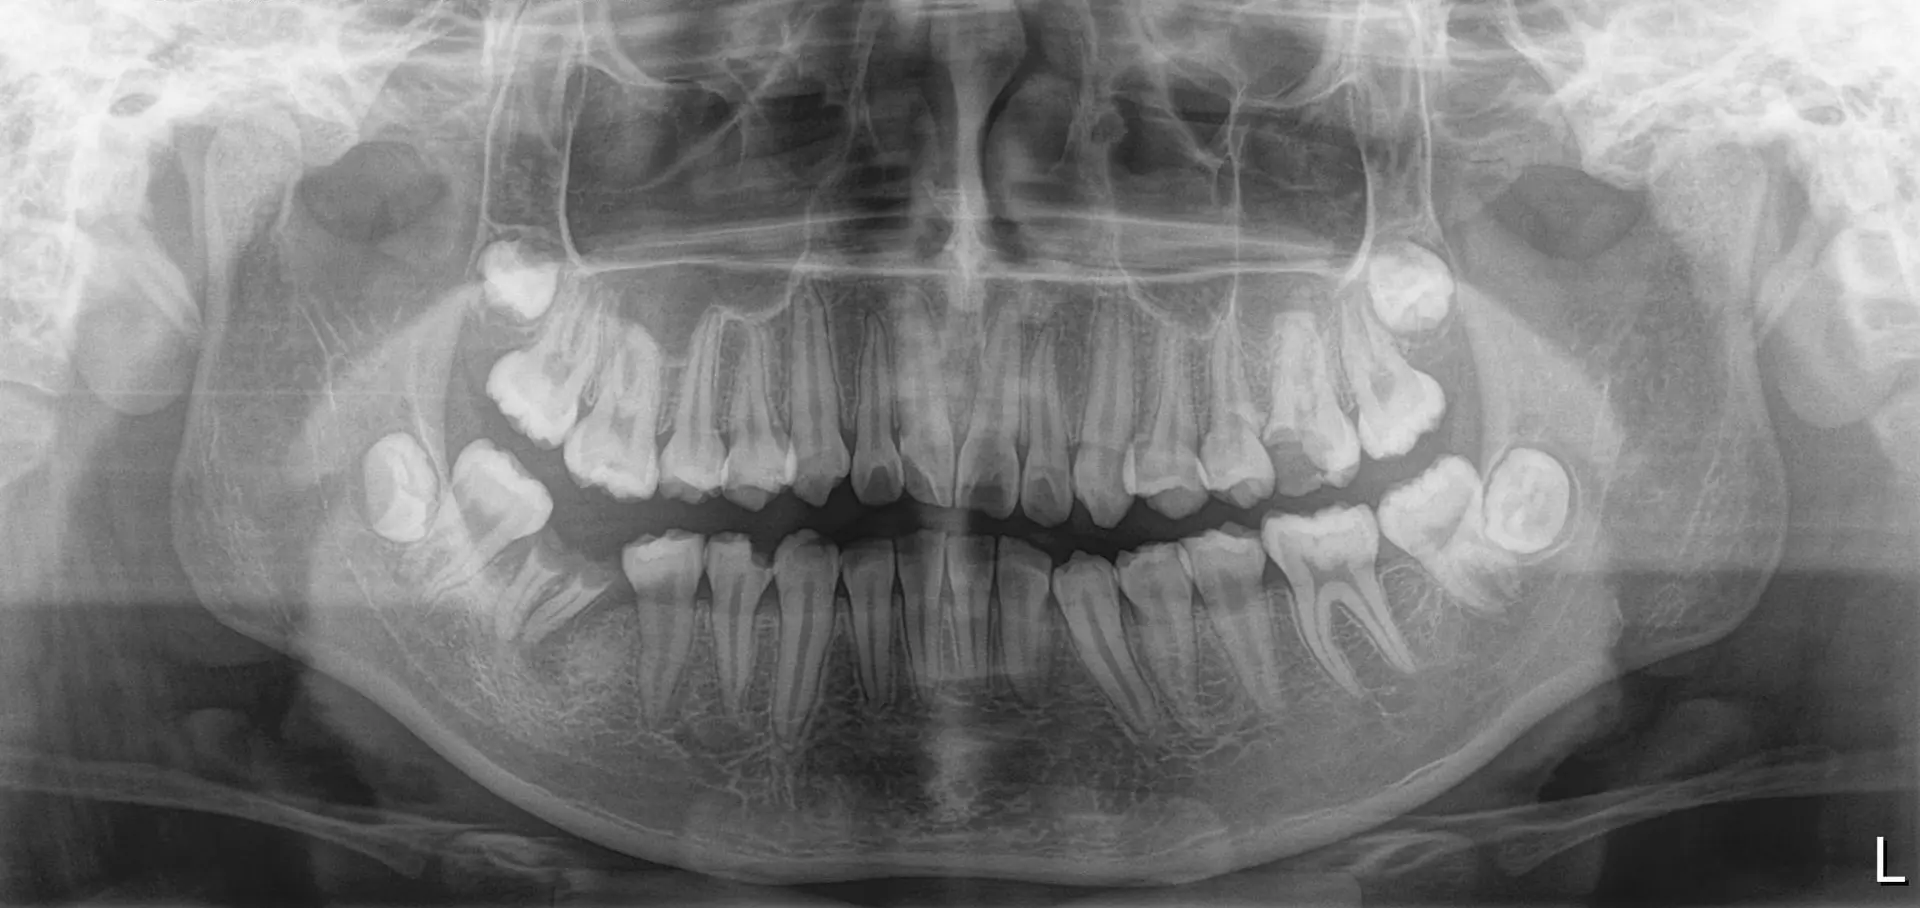

RX PANORÁMICA

Obtenemos una imagen amplia y continua de toda la cavidad bucal en una sola toma. En ella se observan el maxilar superior e inferior, los dientes, las articulaciones temporomandibulares, los senos maxilares y parte de las estructuras óseas vecinas.